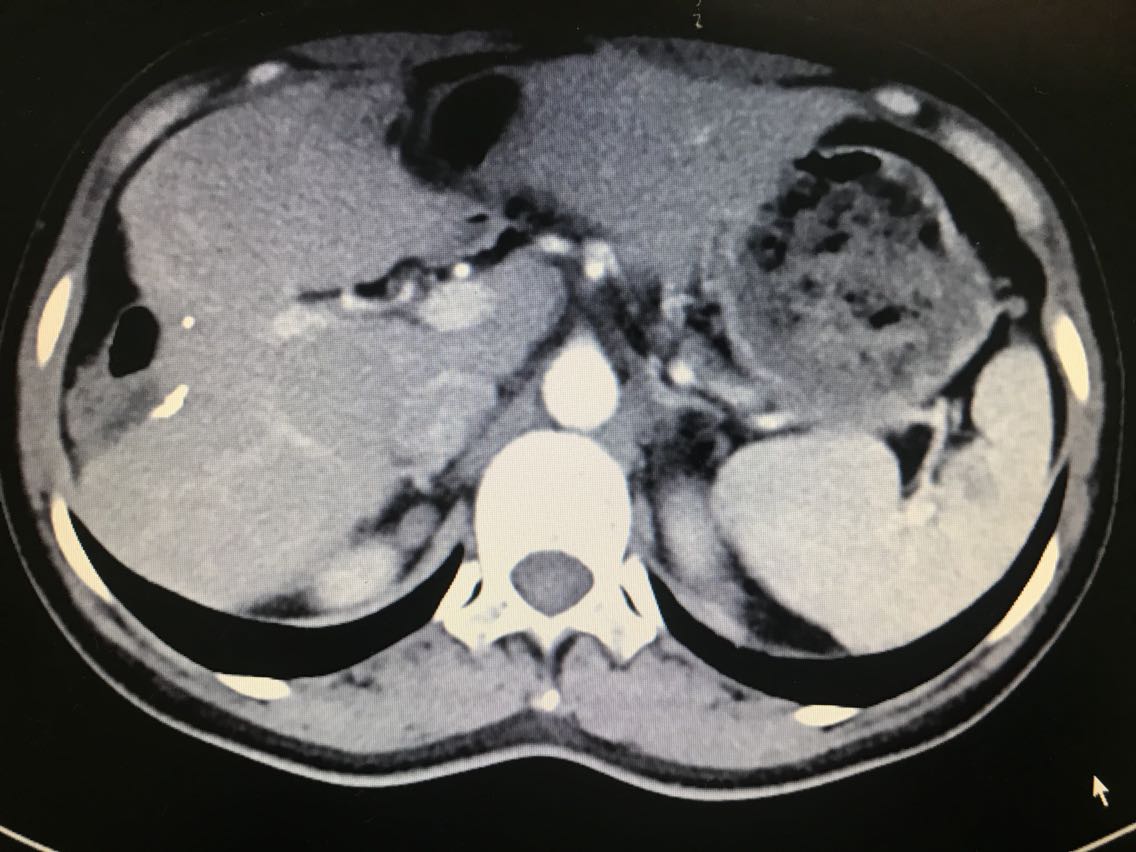

查体无特殊。 辅助检查: 全腹CT:右侧肾上腺占位。

诊断:1.原发性醛固酮增多症(右侧优势侧)2.右侧肾上腺结节 治疗:腹腔镜右肾上腺肿瘤切除术 术中见:右侧肾上腺肿物与肾周紧密粘连,金黄色,约1.0*1.8*1.0cm大小。剖视肿瘤为鱼肉状实性肿物。